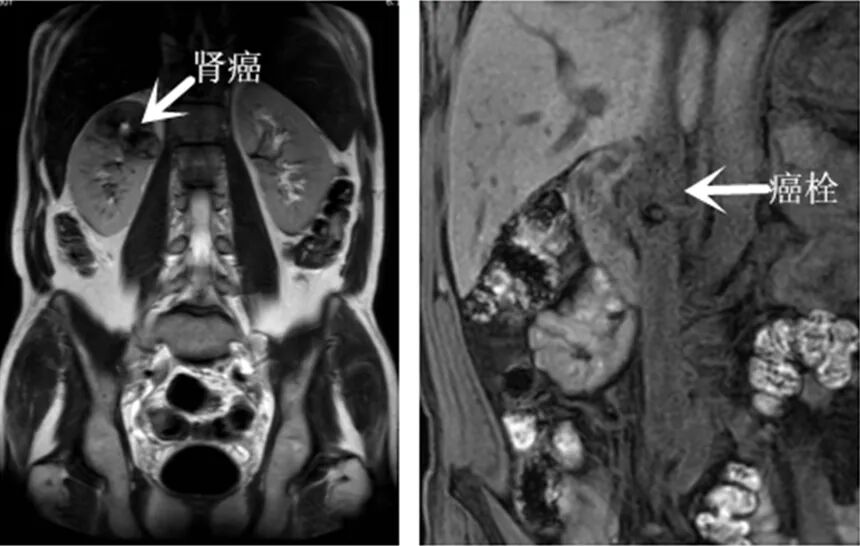

兰州大学第二医院 我院泌尿外科成功开展一例达芬奇机器人辅助微创右肾癌根治并下腔静脉II级癌栓切除术 泌尿外科新闻资讯 近日,兰大二院泌尿外科三病区杨宁强副主任医师团队为一位50岁右肾癌合并腔静脉II级癌栓的男性患者成功实施了“达芬奇机器人辅助微创右肾癌根治性切除术并腔静脉癌栓切除术”,成功挽救了患者的生命。 患者体检发现肾脏占位性病变,就诊于当地医院行相关检查后诊断为右肾癌合并下腔静脉癌栓,同时合并糖尿病、颈动脉斑块,颈内静脉血栓及冠状动脉斑块等疾病。肾癌合并下腔静脉II级癌栓属临床少见病例,且患者患有多种基础疾病,手术风险极高。 鉴于患者的复杂病情经术前MDT讨论后实施了达芬奇机器人辅助下右肾癌根治+下腔静脉瘤栓切除术,术中血管阻断完全,取出癌栓长约5.2cm,病灶清除彻底,术中出血约50ml,手术顺利,患者康复出院。 【相关阅读】 肾癌合并下腔静脉癌栓是癌细胞突破肾脏血管,延伸进入下腔静脉,形成癌栓,相当于在人体内安装了一颗不定时炸弹,术中一旦癌栓脱落,随血流进入肺动脉,形成肺栓塞后,易发生猝死。兰大二院泌尿外科作为国家临床重点专科,在泌尿外科各个高精尖领域手术方面充分发挥了达芬奇手术机器人的各项优势,以先进的理念和技术及多样化的诊疗手段为广大患者的健康保驾护航。